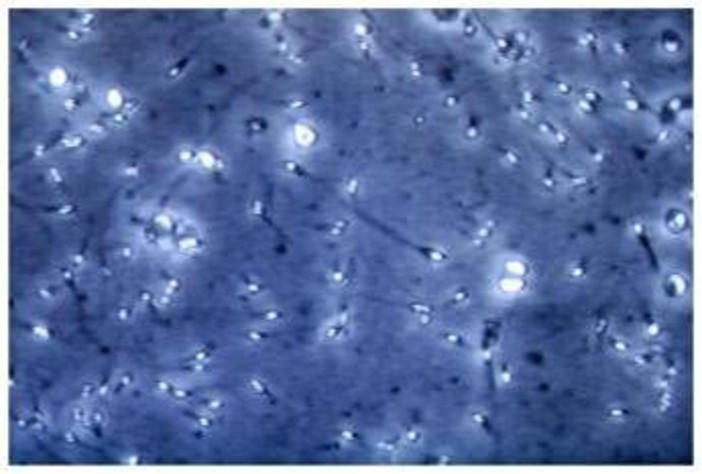

Analizzando campioni di liquido seminale provenienti da uomini sani con parametri nella norma, i ricercatori hanno individuato microplastiche in tutti i sei campioni esaminati. Le particelle osservate hanno dimensioni molto piccole, comprese tra circa 2 e 13 micrometri. Si tratta di dimensioni estremamente ridotte: pochi micrometri corrispondono infatti a grandezze paragonabili a quelle degli spermatozoi stessi, la cui testa ha un diametro di circa 5-8 micrometri.

"Uno degli aspetti più rilevanti emersi dallo studio è che le microplastiche, pur essendo presenti nel liquido seminale, non aderiscono agli spermatozoi e non penetrano al loro interno", si legge nello studio. Le particelle risultano disperse nel plasma seminale e coesistono con le cellule senza stabilire un’interazione diretta. "Questo dato è importante perché indica che, almeno per le microplastiche di queste dimensioni, non osserviamo un contatto diretto con gli spermatozoi - sottolinea il professor Andrea Di Nisio dell’Università Pegaso, co-autore dello studio - Ciò non significa che il problema sia irrilevante, ma che eventuali effetti potrebbero essere mediati da meccanismi indiretti, legati piuttosto alle strutture riproduttive che le microplastiche attraversano prima di arrivare al liquido seminale, come ad esempio testicoli, epididimo e prostata".